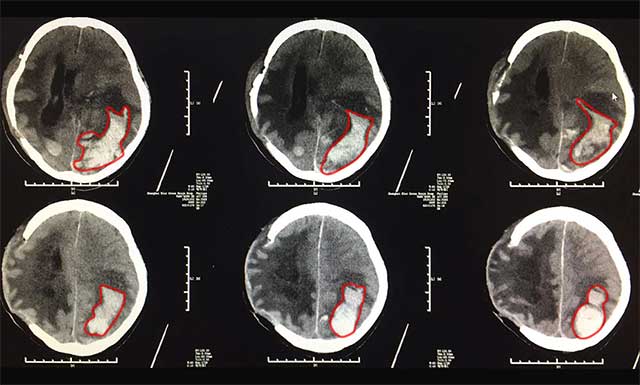

▲标记处为出血部位,患者情况危急

2月16日早上,医生查房时发现患者李家民瞳孔有散大的情况,眼睛对光反应也消失了,考虑患者有再出血的可能,建议患者立即通过脑卒中“急诊绿色通道”进行头颅CT检查。医院为了缩短脑卒中患者的抢救时间,特设立“急诊绿色通道”, 为脑梗死、脑出血患者急诊救治赢得了宝贵时间。

影像提示,患者脑出血术后改变,潘仁龙主任当机立断,立刻组织了神经外科6B病区吴治群博士进行紧急会诊,患者左侧额颞顶枕叶有一个很大的血肿,根据患者病史、病症及影像学表现,考虑患者这次脑出血为淀粉样脑血管病变或血管畸形破裂所致。并一致认为患者手术指征明显,脑出血情况紧急,出血量也比较多,已经危及生命,必须立即手术,才能挽救患者生命。